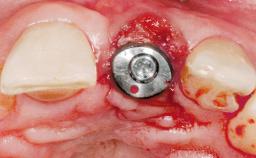

This 43-year-old male patient, a non-smoker, came to our practice because of a fracture of tooth 12 caused by a bicycle accident. Due to the combined para- and infrabony crown and root fracture, tooth extraction, and subsequent implant placement were suggested to the patient as the therapy of choice. The patient had high esthetic expectations with regard to the treatment outcome and asked for an immediate fixed provisional restoration. His individual esthetic risk profile summed up to a medium esthetic risk.

| Placement Protocol | Immediate implant placement |

| Tooth Site | Maxillary incisor or canine |

| Socket Morphology | Single-root socket |

| Socket Integrity | Sufficient, with intact bone walls |

| Bone Volume | Sufficient, with intact walls |